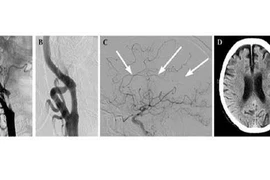

Hẹp động mạch cảnh < 50% thường chưa có biểu hiện lâm sàng. Còn hẹp động mạch cảnh có triệu chứng là biểu hiện của thiếu máu não hay nặng hơn là tai biến mạch máu não (đột quỵ thiếu máu não). Đột quỵ thiếu máu cục bộ là kết quả của tình trạng thiếu oxy trong một phần của não.